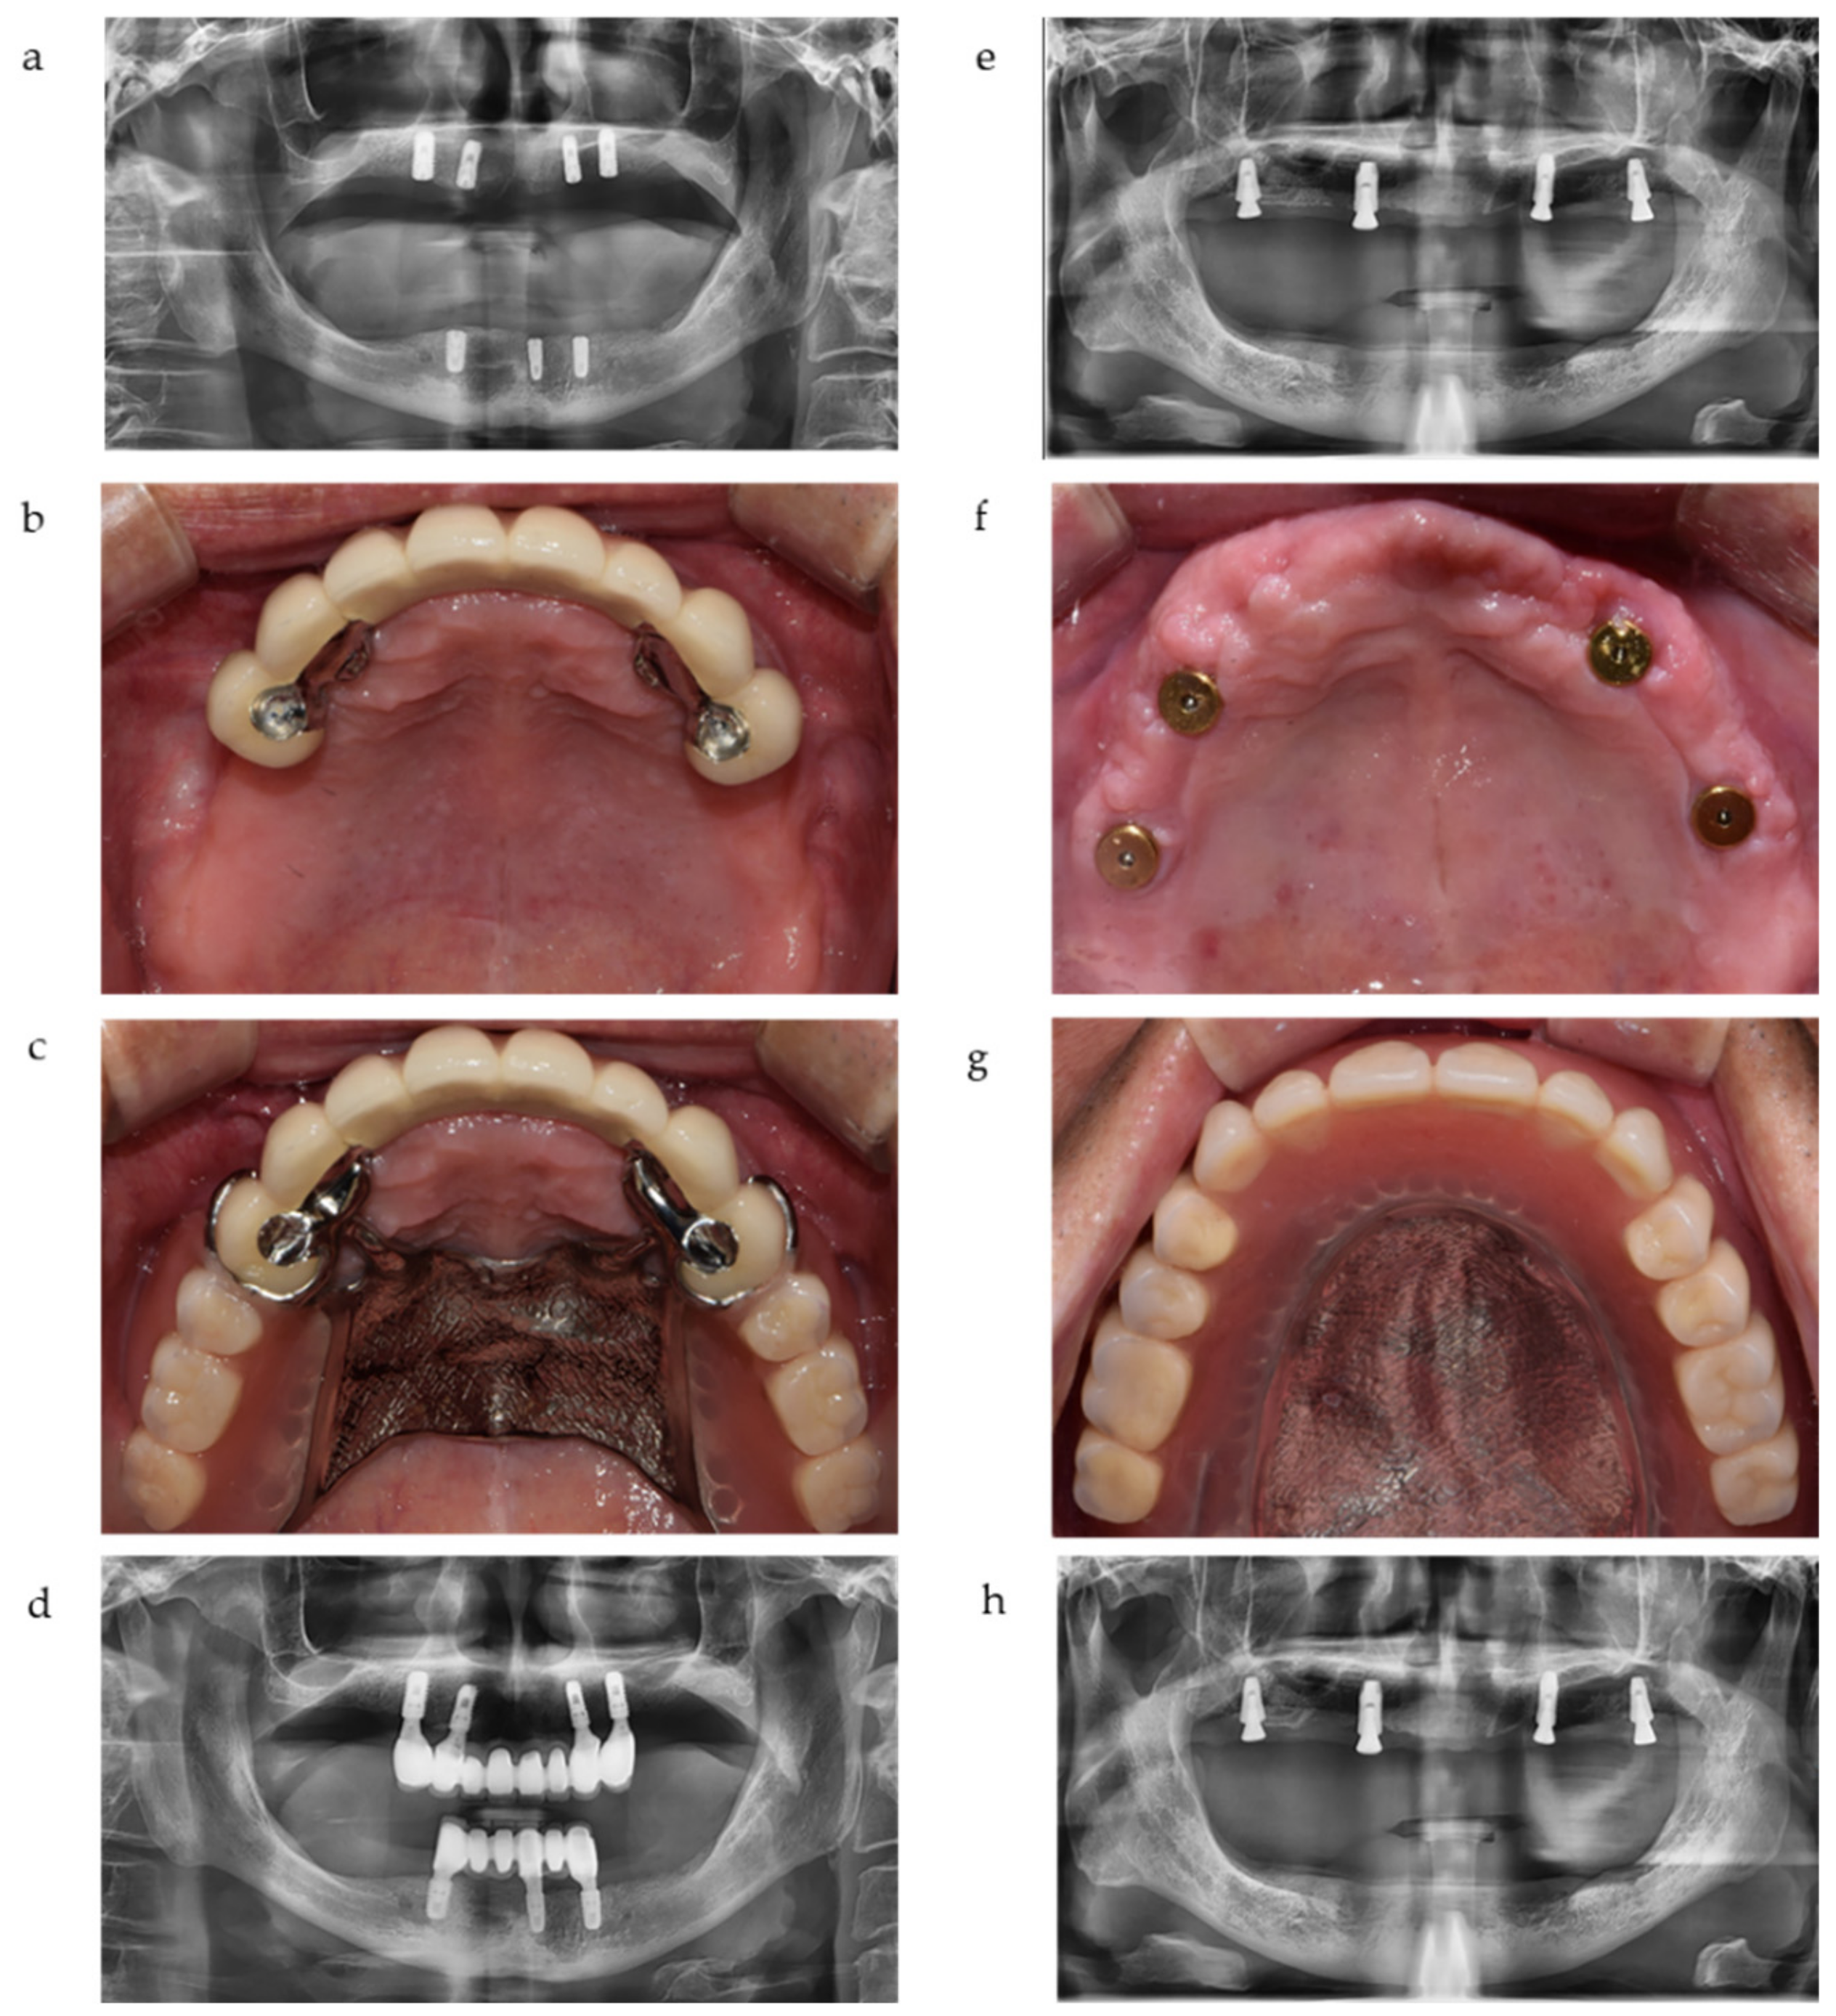

In most cases of IOD, two anterior implants (canine position) and two posterior implants (first molar position) were used for better force distribution. These implants were attached by magnets beneath the IOD as shown in Figure 1. Clinical and radiographic assessments were performed on a total of 145 implants during the observation period.

Figure 1. Representative cases of implant-crown-retained removable partial dentures (IC-RPD) and implant overdentures (IOD) in this study. (a) Implants were placed in anterior positions due to anatomical limitations. (b) Intraoral view of IC-RPD case. (c) Delivery of IC-RPD. (d) Panoramic radiograph of IC-RPD case. (e) Four implants were placed with lateral sinus floor elevation and bone augmentation. (f) Intraoral view of IOD case. (g) Delivery of IOD. (h) Panoramic radiograph of IOD case.